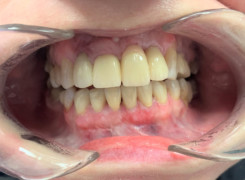

Pan Ryszard trafił do Naszego Gabinetu z jasno sprecyzowanym oczekiwaniem. Miał 84 lata i chciał odzyskać możliwość swobodnego spożywania posiłków oraz poprawienia sobie komfortu życia a także prosił aby przywrócić mu piękny uśmiech jakim cieszył się przed laty. Już na początku pierwszej rozmowy zastrzegł, że interesuje go wyłączenie rozwiązanie uzupełnieniem protetycznym stałym. Nie miał zamiaru użytkować żadnych protez ruchomych. Mając na uwadze powyższe wykonaliśmy Panu Ryszardowi zdjęcie pantomograficzne oraz badanie tomograficzne szczęki i żuchwy na postawie których zapanowywaliśmy Pacjentowi optymalne rozwiązanie – stałe uzupełnienie protetyczne w postaci 28 koron cyrkonowych zamontowanych do dwóch belek cyrkonowych które będą przymocowane do 16 implantów w konfiguracji 8 wszczepów w szczęcie 8 w żuchwie. Po omówieniu powyższego planu przystąpiliśmy do Wspólnej pracy której efekty w poszczególnych etapach prezentujemy poniżej.